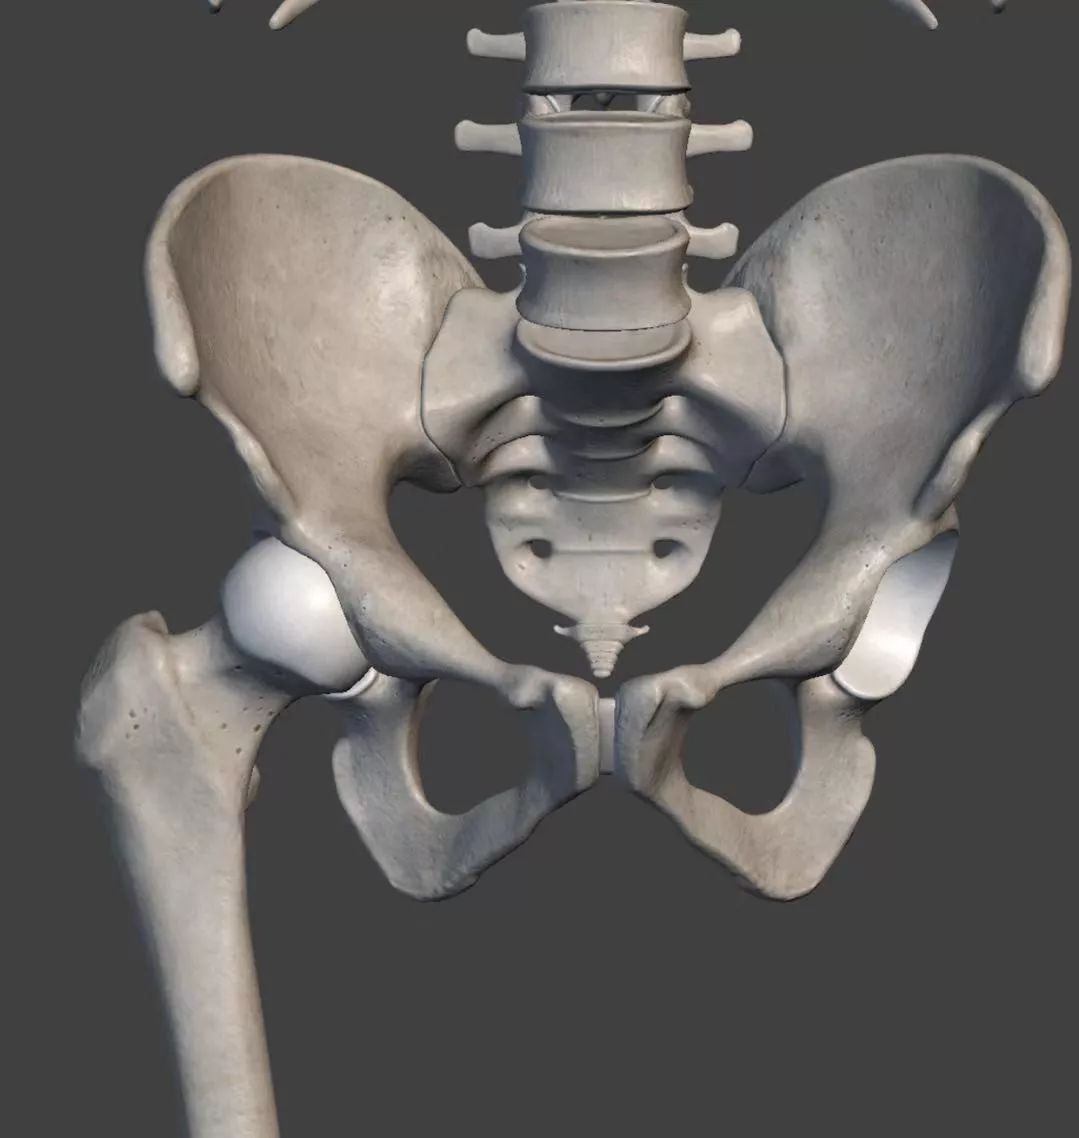

髋骨_有来医生

图片尺寸1600x930